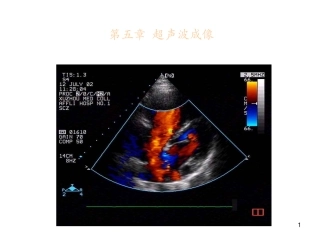

1第五章超声波成像2第二章超声波成像•主要内容•2.1超声波的物理性质•2.2超声探测的物理基础•2.3超声成像系统工作原理•2.4超声多普勒成...